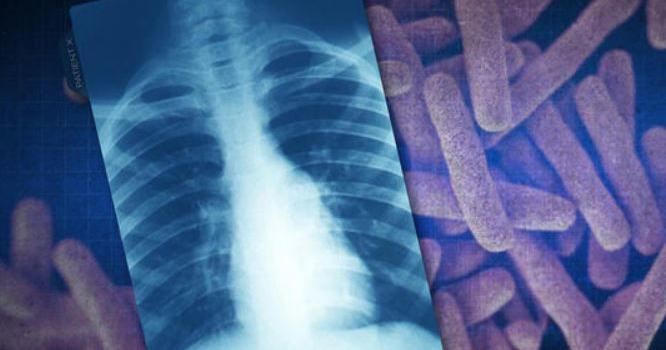

NEW YORK (AP) — The number of people diagnosed with tuberculosis worldwide rose again last year, eclipsing 2023's record total , World Health Organization officials said Wednesday.

About 8.3 million people across the globe were reported as newly diagnosed with TB in 2024. Not all infections are diagnosed and the new numbers represent 78% of the estimated number of people who actually fell ill last year, the WHO noted.

WHO officials see the increase as an indication that screening and treatment are improving after health care disruptions during the COVID-19 pandemic. Globally, the number of deaths caused by TB fell in 2024 to 1.23 million, down from 1.25 million the year before.

U.S. tuberculosis cases continued to rise last year — reaching the highest level in more than a dozen year